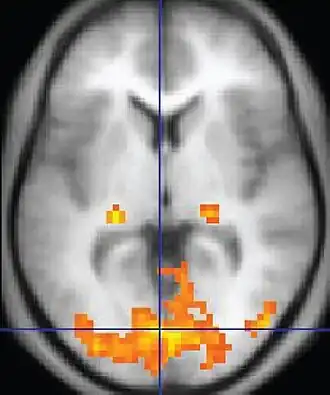

In modern neuroscience, neuroimaging techniques are of particular importance as the main research methods of neuroscientists. Functional magnetic resonance imaging (fMRI) measures changes in the magnetic field of the brain associated with blood flow. Areas of increased blood flow indicate that the corresponding brain region is particularly active. Positron emission tomography (PET) uses radioactive substances to detect a range of metabolic changes in the brain. Electroencephalography (EEG) measures the electrical activity of the brain, usually by placing electrodes on the scalp and measuring the voltage differences between them. These techniques are often employed to measure brain changes under particular circumstances, for example, while engaged in a specific cognitive task. Important insights are also gained from patients and laboratory animals with brain damage, helping neuroscientists understand the function of the damaged area and how its absence affects the remaining brain.[165]